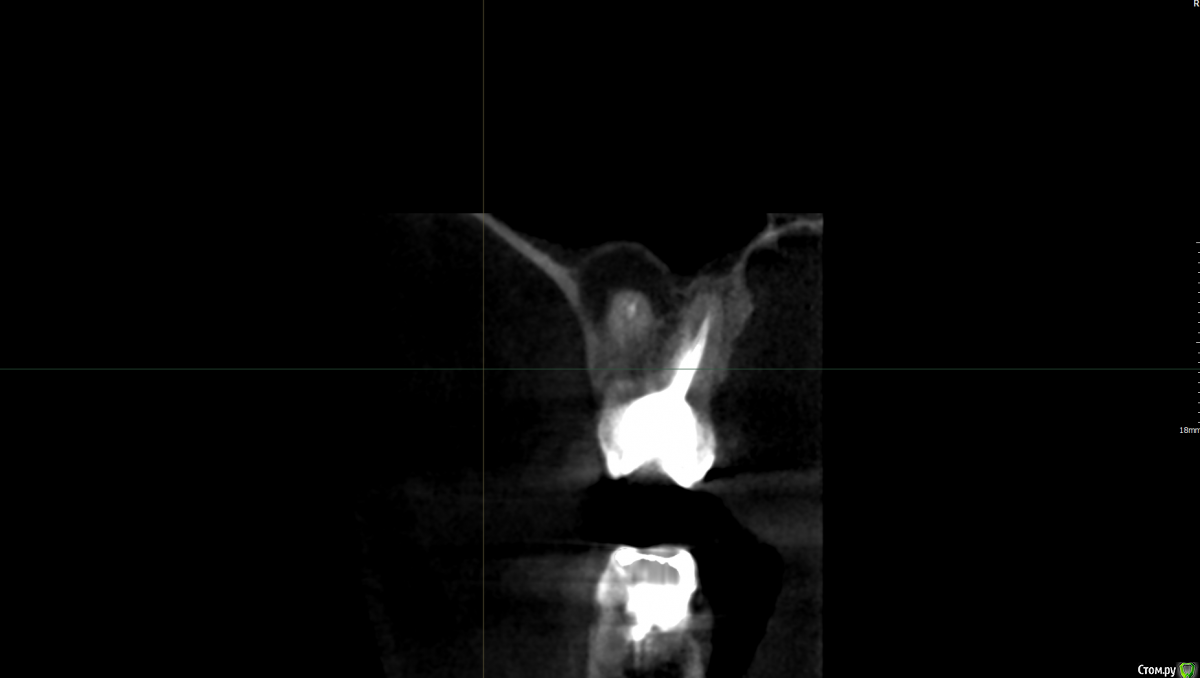

AlR Опубликовано 8 сентября, 2017 Автор Поделиться Опубликовано 8 сентября, 2017 (изменено) Вот образ диска, что дали когда делал снимок повторно пару часов назад https://yadi.sk/d/R7VKk0173MichUну и два скрина от туда Зуб сверху слева второй. Говорит удалять, шанс вылечить не больше 25%. Вроде как киста, так сложно лечится что ли? нифига не болит, постучал по зубам, как то все одинаково было) нигде не гремит Можно как то её победить не удалая зуб, а то бюджет на имплат пока что не запланирован Может это свищь? Очень похоже было на одну из фоток тут. Еще вспомнил, до этого зуб как бы чесался и как бы хотел наружу вылезти, не знаю как описать это ощущение. Фото самого сделать не могу, но на десне совсем маленький прыщик такой под цвет десны. Изменено 8 сентября, 2017 пользователем AlR Ссылка на комментарий

red_butler Опубликовано 8 сентября, 2017 Поделиться Опубликовано 8 сентября, 2017 Это периодонтит, требуется повторное лечение корневых каналов. Ссылка на комментарий

red_butler Опубликовано 8 сентября, 2017 Поделиться Опубликовано 8 сентября, 2017 Если судить только по снимку, то зуб удалять не нужно. Ссылка на комментарий